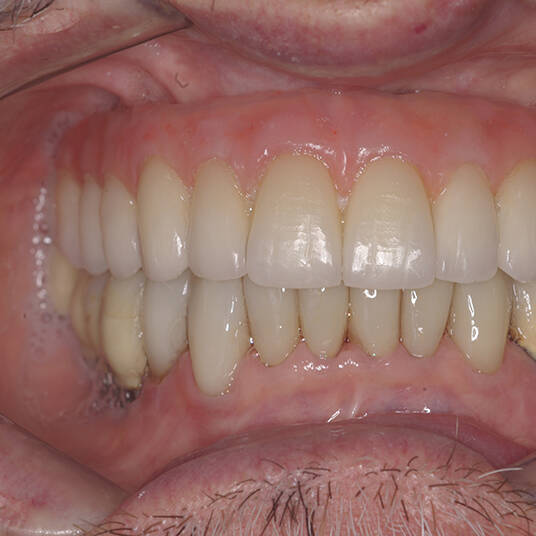

Na Clínica Pontes Odontologia, somos referência em implantes dentários em Fortaleza, oferecendo tratamentos de alta qualidade e tecnologia de ponta. Os implantes dentários são estruturas de titânio posicionadas cirurgicamente no osso maxilar ou mandibular para substituir as raízes dos dentes ausentes. Essa técnica permite a fixação de próteses personalizadas, restaurando a função mastigatória, a estética e a autoestima dos nossos pacientes.

Utilizamos a tecnologia CAD CAM, um sistema avançado que possibilita a confecção precisa das próteses dentárias diretamente sobre os implantes. Esse método inovador garante um ajuste perfeito, um resultado estético superior e proporciona muito mais conforto e durabilidade. Com o CAD CAM, nossos pacientes contam com um processo mais rápido e previsível para alcançar o sorriso desejado.